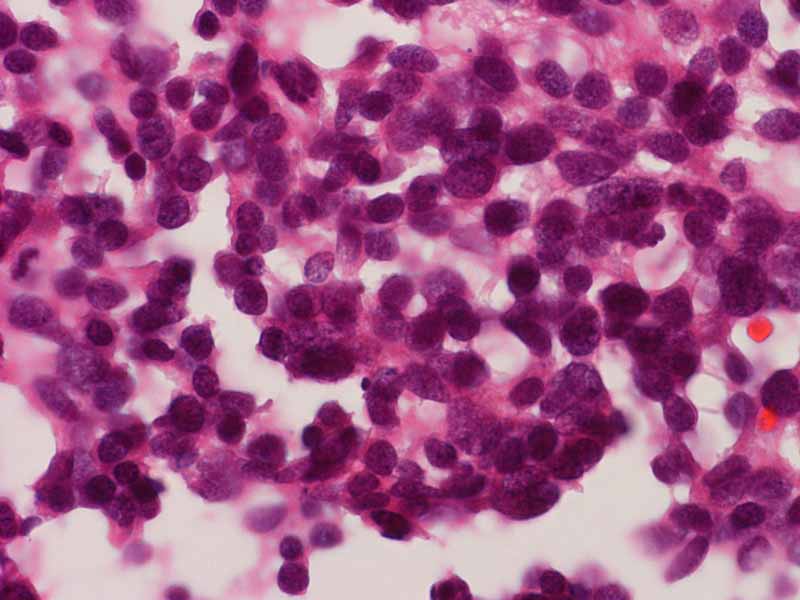

Synaptophysin

Merkel cell carcinoma is a neuroendocrine neoplasm and is positive for synaptophysin and chromogranin (not shown here).